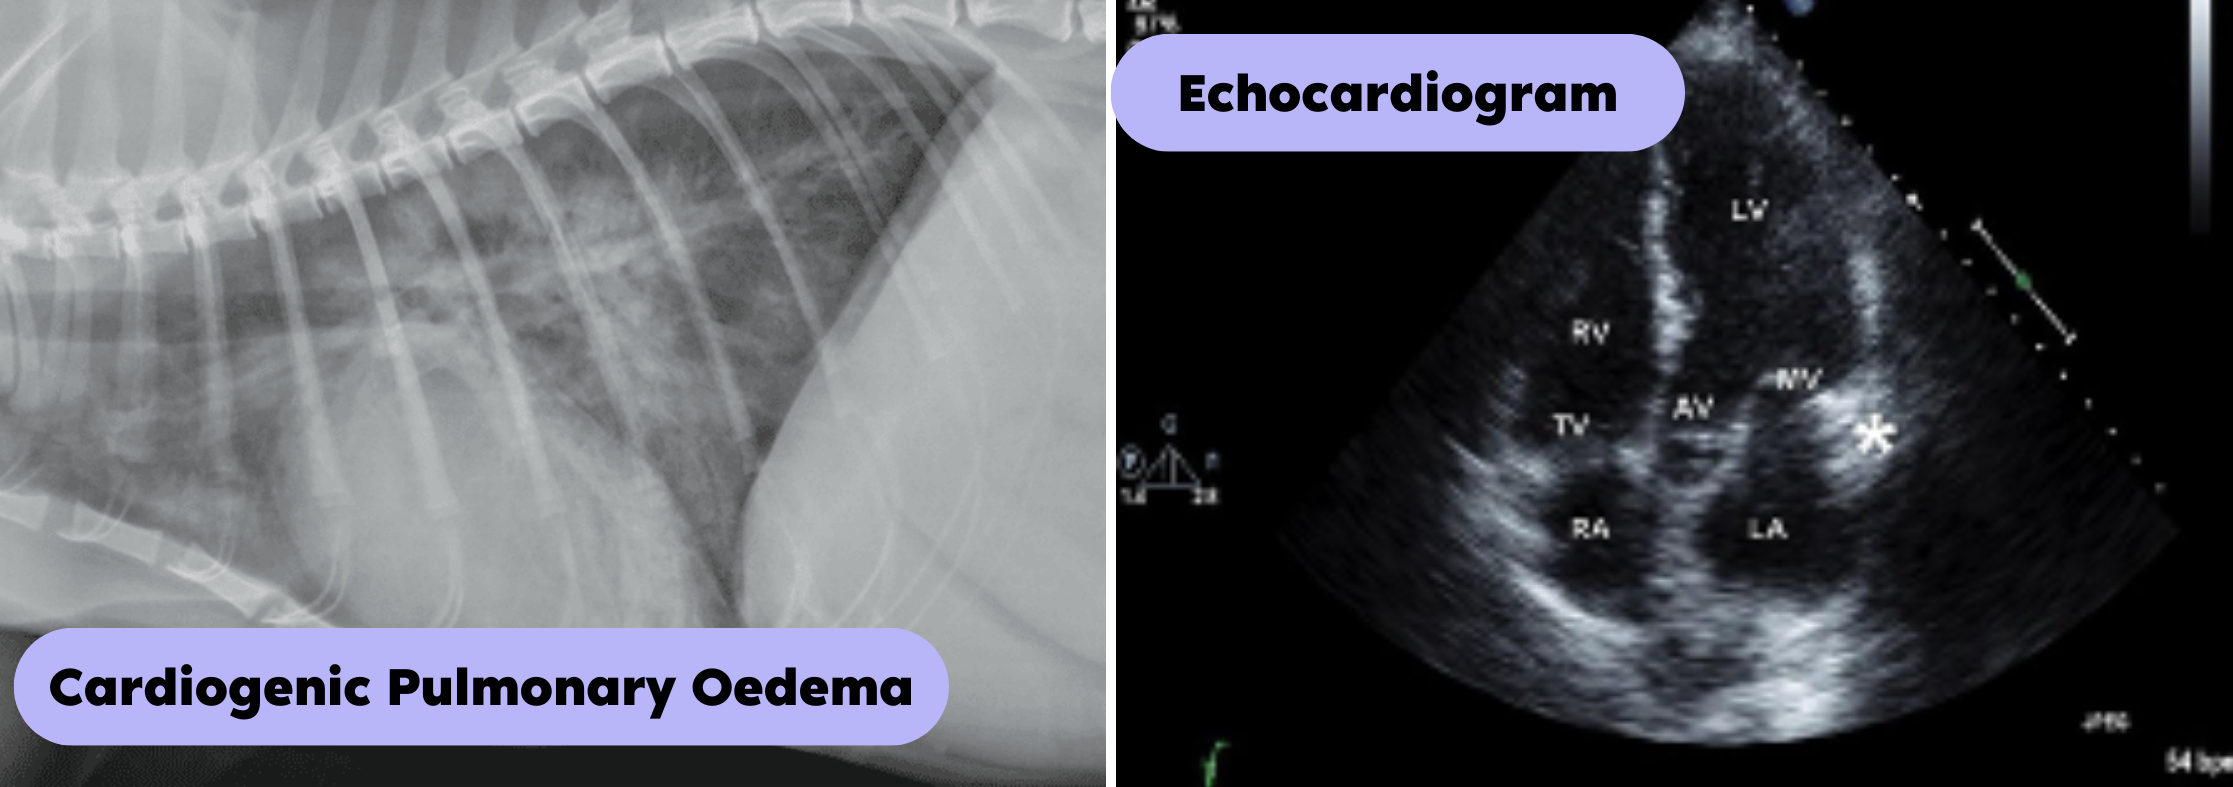

如果醫生懷疑病人有充血性心力衰竭,他們通常會進行胸部 X 光 (Thoracic radiology)檢查,看看是否有證據表明 :

· (A) 心臟擴大(Heart enlargement)- 血液滯留於心臟;

· (B) 與肺積水一致的肺部混濁,或與胸腔積液一致的胸腔積液。

正如上兩篇心臟病診斷所述般, 下一步多數會安排進行心臟超聲波 (Echocardiogram),如果有心律不正的情況便需進行心電圖(Electrocardiogram)檢查,還有常規血液檢查。